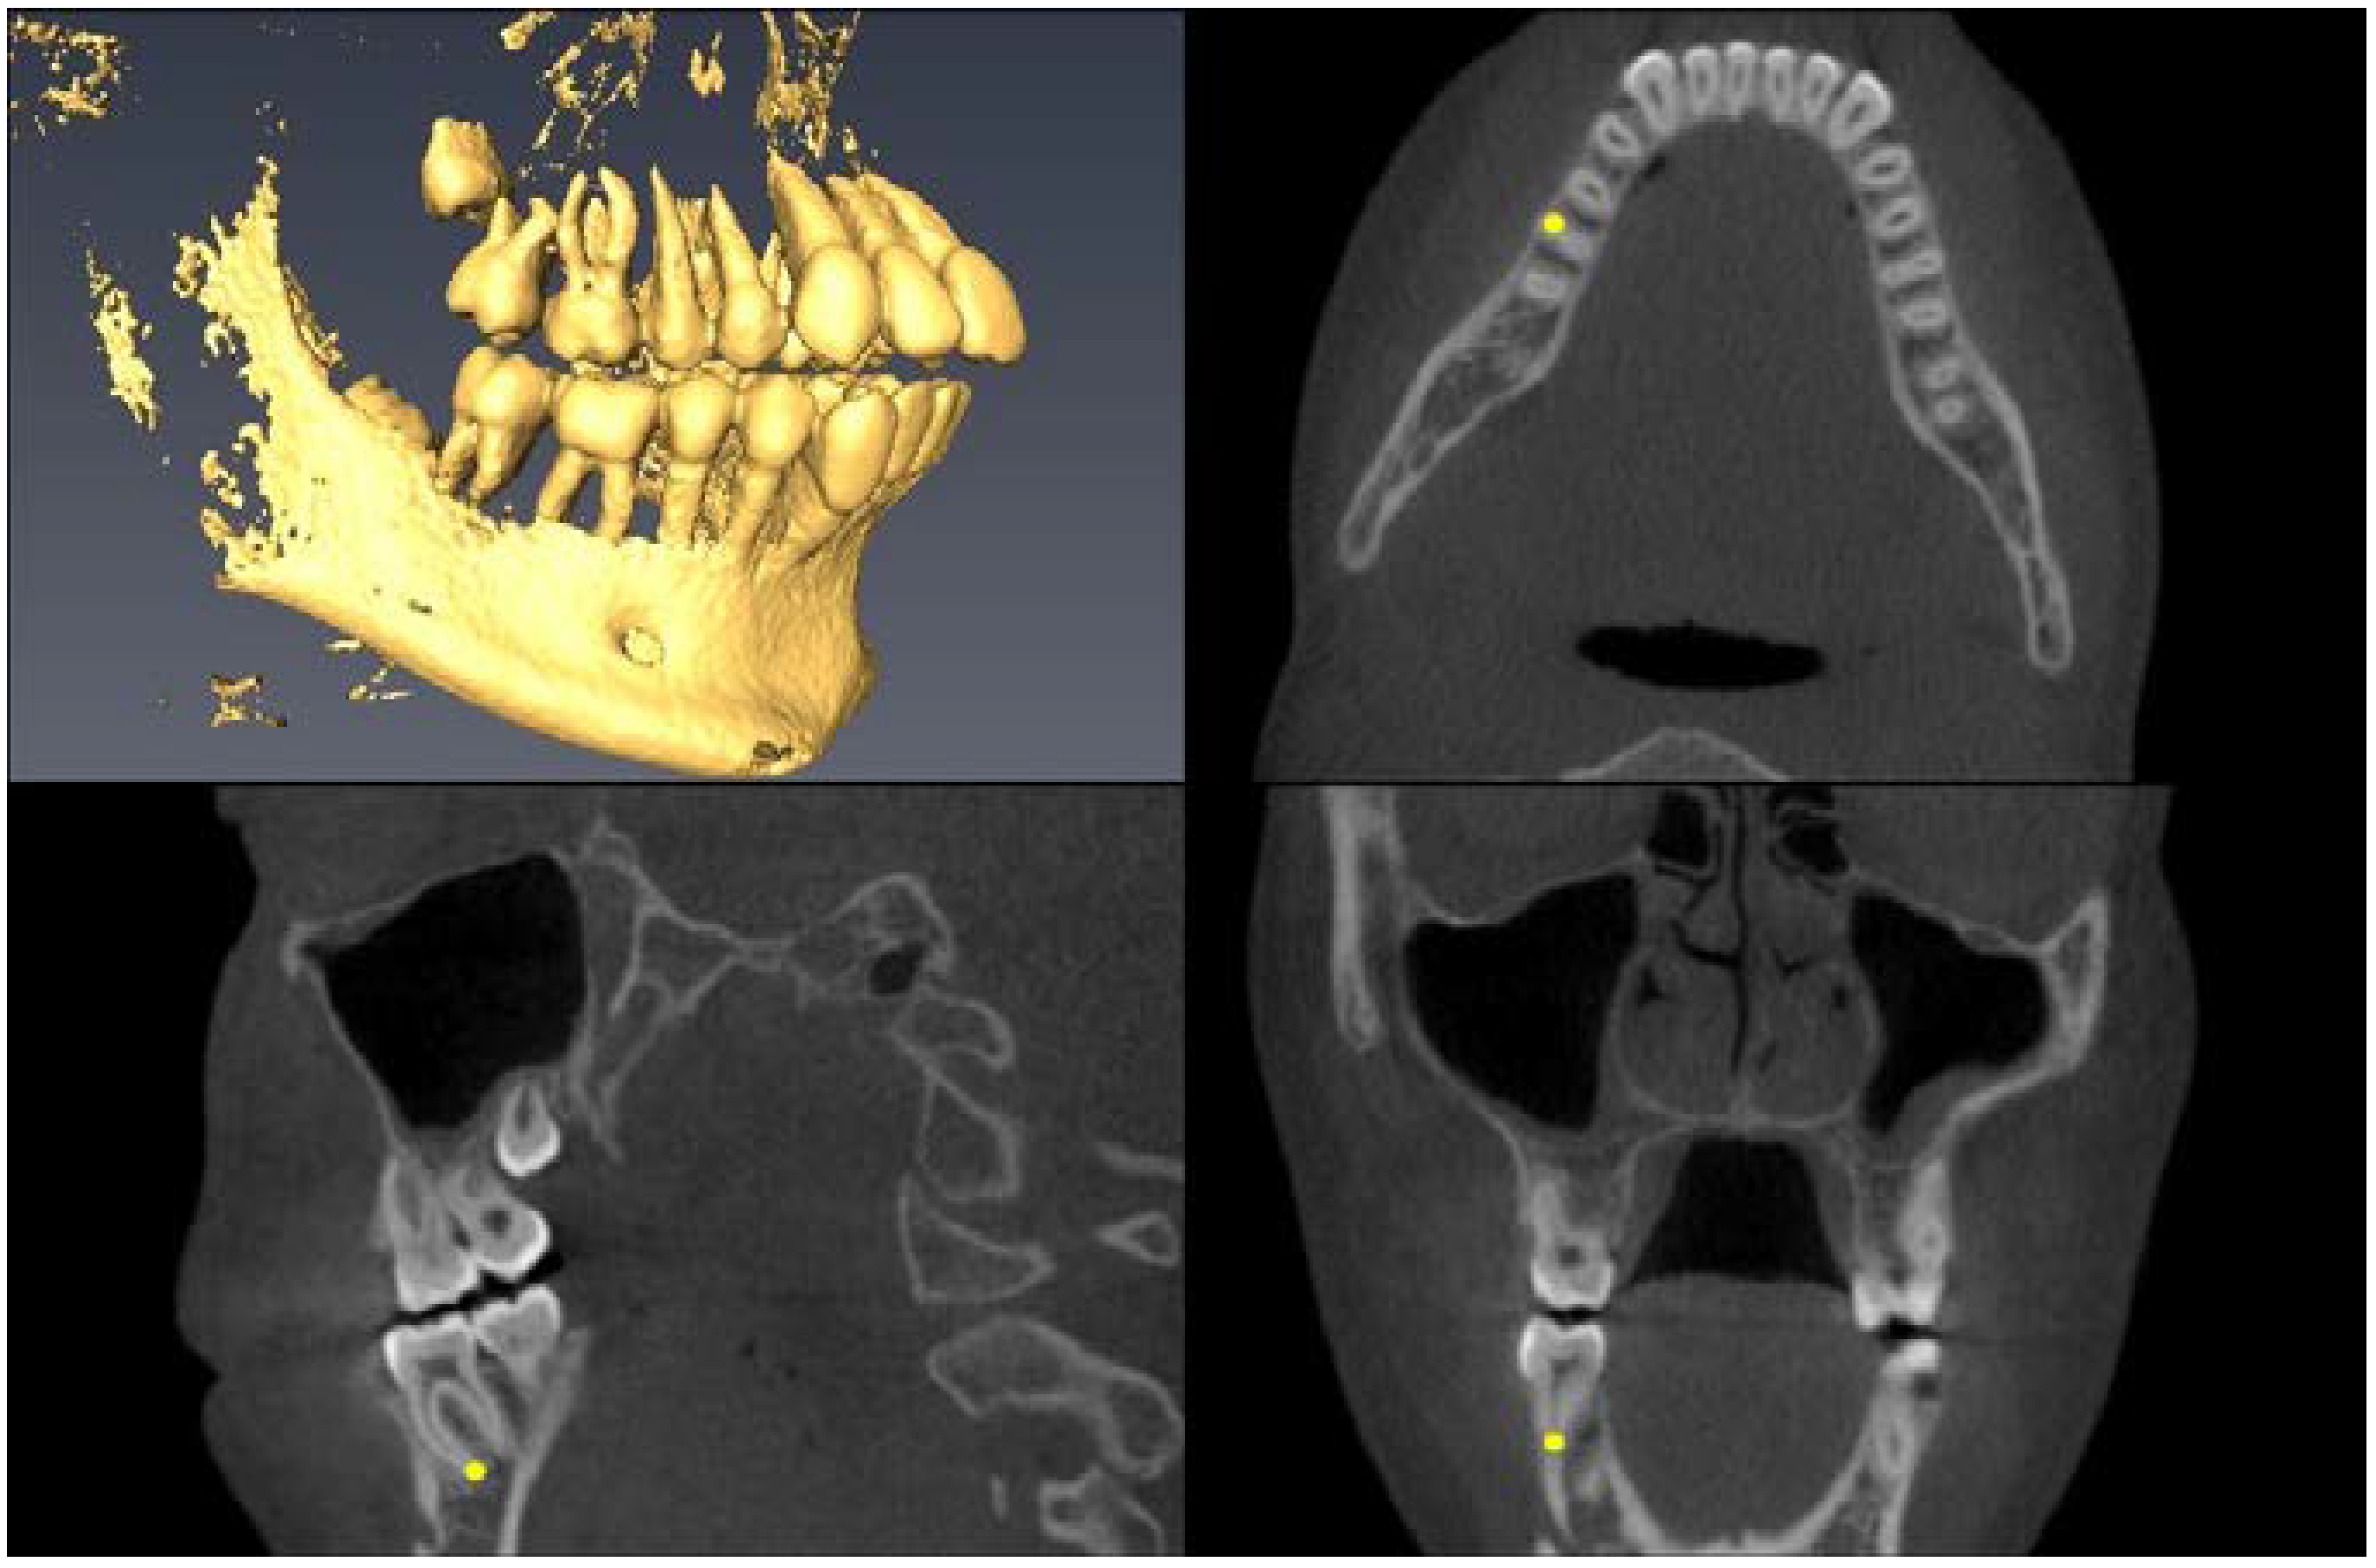

| Landmark Description | 3D View (Upper Left), Axial View (Upper Right), Sagittal View (Lower Left), Coronal View (Lower Right) |

| Lower First Molar Pulp Chamber =center of largest cross-sectional pulp chamber area | ![]() |